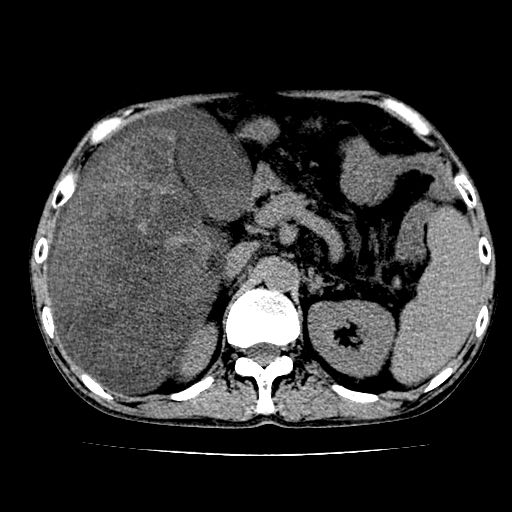

男,55岁,发现“肝硬化”5年,现腰疼、腹胀10余日,巩膜黄染、腹稍胀,肝肋下3指,质硬无压疼,移动性+,血生化:总胆、直胆、间胆均升高。

g1:肝硬化、脾大、腹水。

2:脂肪肝。

3:弥漫性肝癌待排。

肝硬化,脾大,腹水

脂肪肝

肝内多发低密度灶(建议增强扫描除外肝癌)

肝脾肿大,脂肪肝,腹水。建议增强除外肝癌。